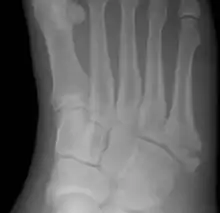

Jones fracture

A Jones fracture is a break in a specific part of the fifth metatarsal of the foot between the base and middle part[8] known for its high rate of delayed healing or nonunion.[4] It results in pain near the midportion of the foot on the outside.[2] There may also be bruising and difficulty walking.[3] Onset is generally sudden.[4]

| Jones fracture as seen on Xray | |